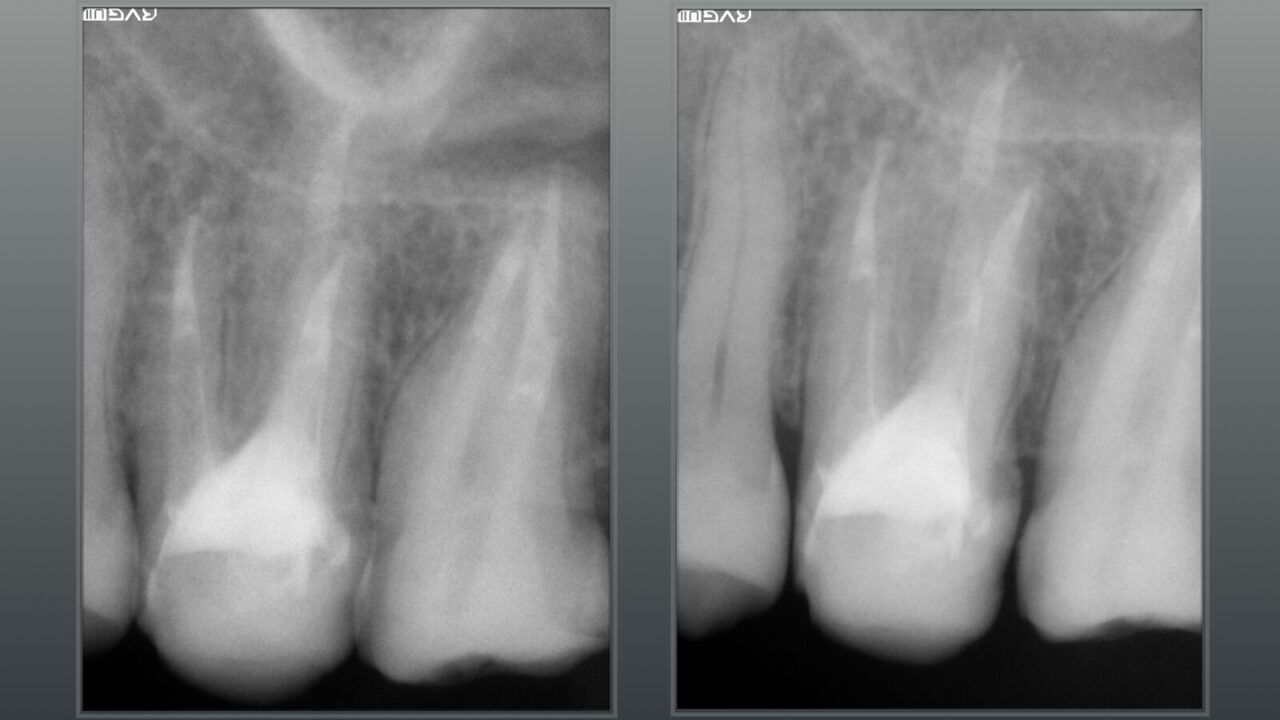

術後のレントゲン写真、術前のレントゲン写真と比べると骨吸収像が改善され骨の再生が確認できます。

次回より本格的な根管治療を行うための準備をしました。CTで根管の内容物がきちんと取り除かれている事が確認できれば、次回はバイオセラミックを用いた根管充填になります。